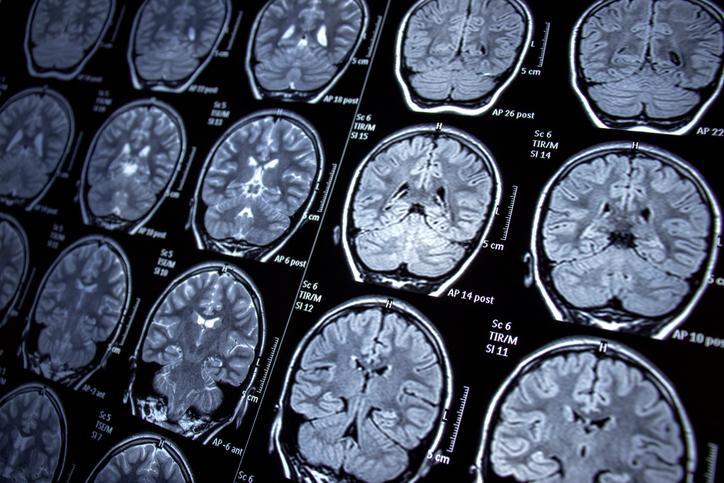

A woman in Australia who complained of stomach upset, forgetfulness and depression had a 3-inch worm removed from her brain in what doctors say was a first.